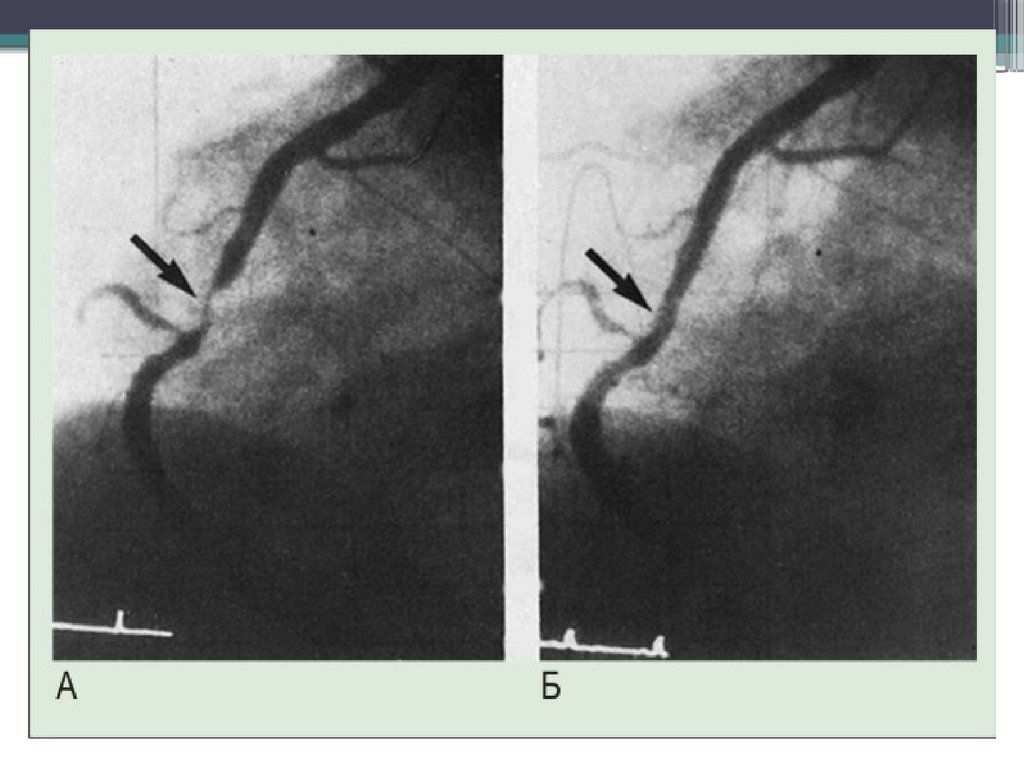

ОКС без подъема сегмента ST

Неокклюзирующий(зачастую реканализированный тромб в просвете крупной

коронарной артерии;

Окклюзия коронарной артерии мелкого калибра (1-2 мм диаметра);

Неокклюзирующий

тромб

16.

17.

18.

19.